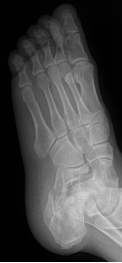

痛风

嘌呤代谢紊乱,以体液、血液中尿酸增加及尿酸盐沉着于各种间叶组织内引起炎症反应

好发于男性,发病高峰40-60岁

以第1跖趾关节最为多见

早期周围软组织肿胀,出现局限骨质硬化,晚期关节面边缘出现囊状、穿凿状骨质缺损,关节间隙可变窄,关节面不光整,晚期骨赘形成可使骨端增大

68Y,M